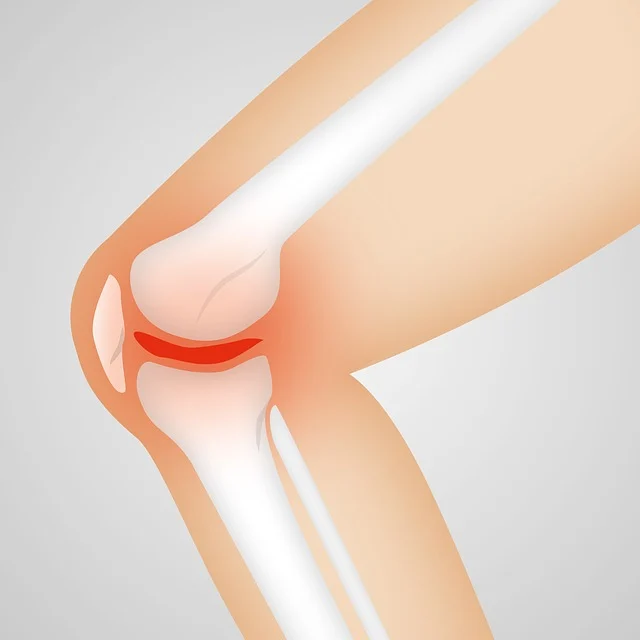

무릎 관절 건강을 위한 필수 영양제

음식만으로 충분한 영양소를 섭취하기 어려울 경우, 관절 건강에 도움이 되는 영양제를 보충하는 것이 좋습니다.

- 글루코사민 & 콘드로이틴

- 연골을 형성하는 성분으로, 관절의 윤활 작용을 돕고 연골 손상을 예방합니다.

- 특히 퇴행성 관절염 예방과 통증 완화에 효과적입니다.